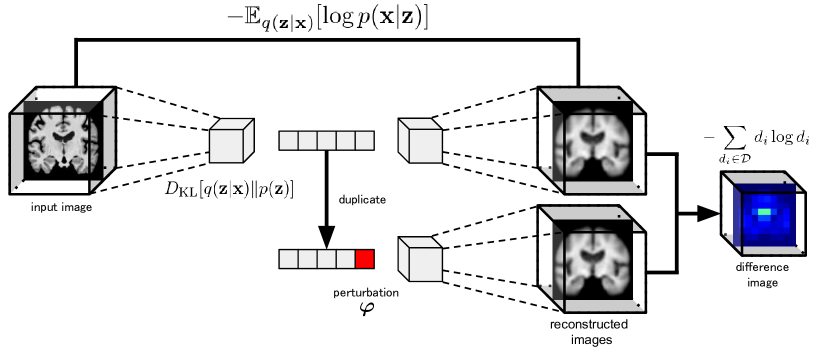

In this paper, we propose the localized variational autoencoder (Loc-VAE), an encoder for acquiring interpretable low-dimensional representation from brain MR images for CBIR. Fig. 1 shows an overview of the proposed Loc-VAE. Loc-VAE is a learning model based on -VAE [14], which provides independent embedding for each dimension while ensuring continuity for each localized region of the brain. The loss function of Loc-VAE consists of the following two terms:

III-B The Local Loss

The key element of Loc-VAE, the local loss, is a constraint that localizes the influence of each dimension of the latent variable . Specifically, we first obtain two reconstructions, one with and one without the one-hot-vector perturbations , which is non-zero in only one dimension randomly selected for the embedding . Then, we obtain the difference between the two reconstructed images as follows111The equations in the text are strictly written, and an intuitive expression that follows the notation used in a typical VAE would be as follows: .:

| (4) |

This means the extent to which a given dimension affects the reconstructed image. Each pixel in the reconstructed image is considered a probability distribution with a dimension of the number of pixels, normalized by the maximum and minimum values of the corresponding pixel in the entire dataset. Local loss is defined as the entropy of the difference image with each pixel , the amplitude of the perturbation , and is a hyperparameter:

| (5) |

In other words, is large when each dimension of is a representation that affects a wide area of the image. This allows learning to occur so that each dimension of the low-dimensional representation has a narrowed range of influence on the corresponding brain MR images and is expected to obtain localized low-dimensional representation.